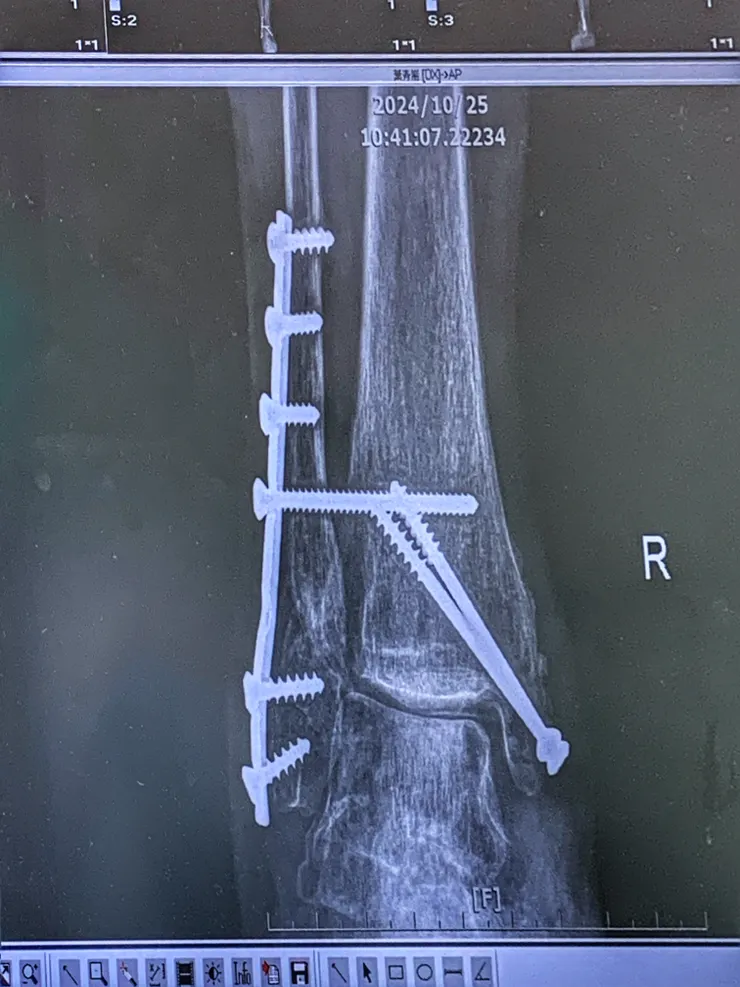

再來轉個身,有夠義氣的朋友傳來蛇年與聖誕節模板,讓還沒有喘口氣的娘娘乾脆把這兩個檔案夾裏面的檔案仔細檢查與整理,過兩天好粉墨登場。未料下午4:44老爺來訊息說我和兒子可以下樓去醫院了,快手收拾一下電腦關機下樓,去醫院取出右腳原先打的一支鋼片、兩支鋼釘的其中一支。

今天取出橫向的鋼釘

整個過程很順利的完成,只是我一直覺得這陌生的場景教人緊張不已!局部麻醉所以我非常清醒之下大大鬆了一口氣。心裡面好感恩,也請他們給我看那支鋼釘長什麼模樣?啊😧就跟螺絲港款😳